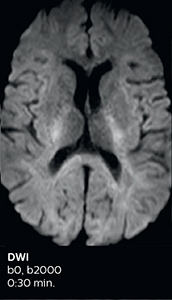

Using MultiBand SENSE allowed the staff to improve their diffusion quality. “Our diffusion sequence was already fast before, about 40 seconds. Now with Elition, it still lasts 40 seconds, but we improved the spatial resolution by 0.2 mm and use high b-values to be more sensitive to visualize changes related to acute stroke,” says Dr. Savatovsky. “We now also developed a high resolution DTI sequence (1.3 x 1.3 x 2 mm) that can be reformatted and takes 2 to 5 minutes depending on the coverage. We use it every time we have a doubt, or when we expect the diffusion to be abnormal but don’t see that on the fast sequence. We occasionally spot small ischemic infarctions that would not have been visible with the regular diffusion sequence.”

This is an example of acute ischemic stroke with distal occlusion of the right posterior cerebral artery. Note the improved visibility of the ischemic territory on the diffusion weighted image with high b-value. The 3D FLAIR shows a distal PCA occlusion. The fast SWIp depicts the thrombus on the isolated second echo image. The total scan time (including SmartBrain, preparations and a fast 3D T1w TSE Gd) is 8:00 minutes.